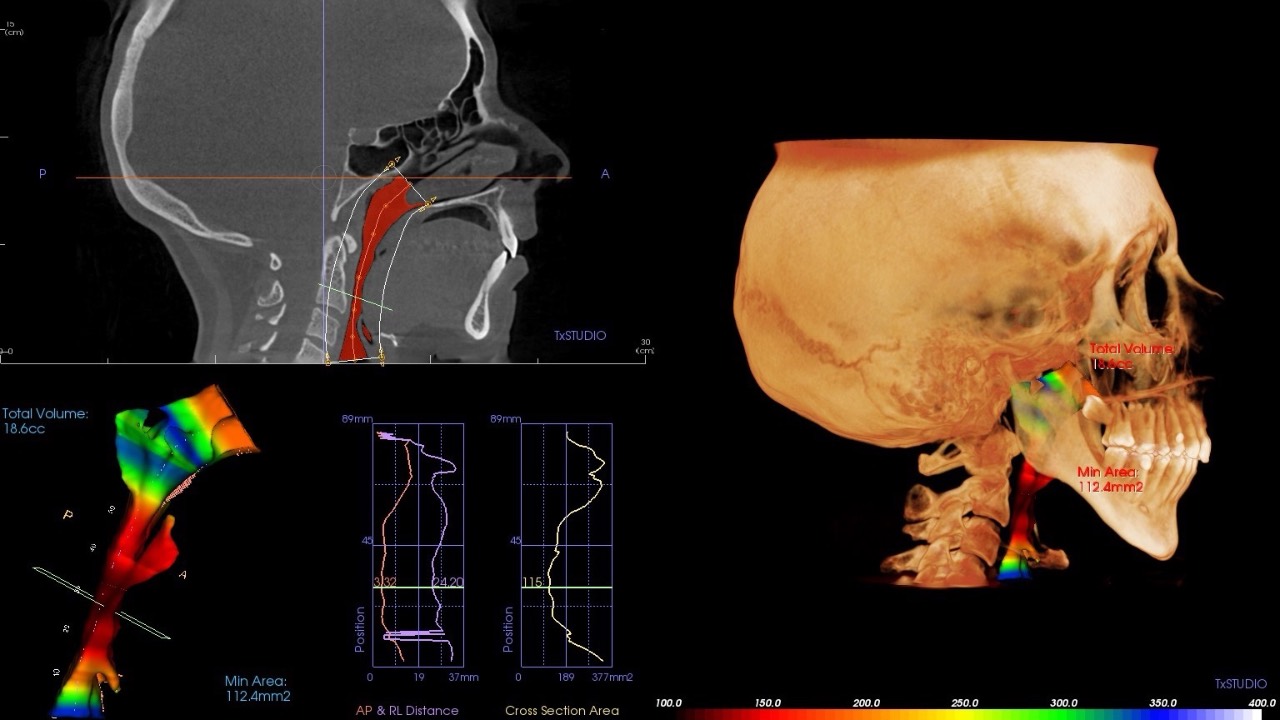

Yag Capsulotomy Timing

Do you know why & when it's best to pull the trigger?...

Determining the optimal timing for a YAG capsulotomy following cataract surgery requires understanding several factors to ensure safety and quality outcomes.

Considerations include complete resolution of post-operative inflammation, positi...